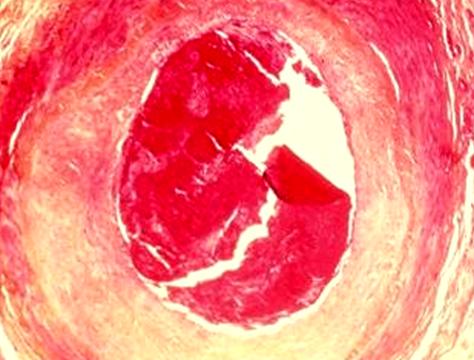

TROMBOSI GRAFT IN SAFENA

Nei primi due decenni dell'era moderna della rivascolarizzazione miocardica, la VGS è stato il condotto più utilizzato in quanto ha una lunghezza sufficiente per bypassare tutte le coronarie ed un diametro, specialmente al di sotto del ginocchio, che si adatta bene ( 3-4 mm ) ai vasi di maggior calibro. Tuttavia essa possiede una struttura morfofunzionale di tipo venoso, non idonea ad un flusso pulsato ad alta pressione come quello arterioso, e dopo l'impianto sull'aorta ascendente essa va incontro ad una iperplasia mio - intimale di tipo reattivo che, se da un lato consente al condotto di adeguarsi alle nuove condizioni emodinamiche, dall'altro riduce la reattività vascolare e può portare al malfunzionamento ed all'occlusione del bypass. Essa viene prelevata utilizzando come punti di repere il malleolo mediale e la cresta tibiale anteriore, legando tutti i rami collaterali ed infine sezionando il condotto per ottenere segmenti di lunghezza sufficiente per i by - pass da confezionare ( la safena viene impiantata invertendone il senso in modo che le valvole presenti nel suo decorso non ostacolino il flusso ematico ).

Nasce dal primo tratto dell'arteria succlavia, scende in basso fino a raggiungere la faccia posteriore della prima cartilagine costale e decorre quindi verticalmente in prossimità delle cartilagini costali, fino al sesto spazio intercostale ove si biforca dando origine all'arteria muscolofrenica ed all'epigastrica superiore ( la quale si esaurisce in vicinanza dell'ombelico anastomizzandosi con i rami della epigastrica inferiore ) e nel suo decorso fornisce rami mediastinici, timici ed intercostali. L'arteria mammaria interna è stata largamente usata come graft arterioso ed in particolare per la rivascolarizzazione del ramo interventricolare anteriore. Essa infatti è, per calibro e per caratteristiche morfologiche, il vaso che più si adatta al ramo interventricolare anteriore ( IVA ). Si tratta di un'arteria elastica la cui lamina elastica interna è intatta, con i vasa vasorum confinati nell'avventizia. L'assenza di discontinuità nella lamina elastica interna comporta una bassa suscettibilità all'aterosclerosi ed all'iperplasia intimale. L'elastina che compone il tessuto elastico della tonaca media ha un basso metabolismo, con una domanda di ossigeno o di substrato ridotta, ottenuta sia per diffusione a partire dal lume arterioso, sia per perfusione attraverso i vasa vasorum. Molti lavori convenzionali e trials randomizzati con lunghi follow-up, hanno dimostrato un'eccellente pervietà dell'AMI su IVA ( >90% ) con incremento della sopravvivenza dei pazienti, a confronto di quelli trattati con grafts in vena safena sull'IVA. L'aterosclerosi tardiva è un'eccezione, mentre colpisce più del 70% dei grafts venosi a 10 anni. Osservazioni recenti suggeriscono che la lamina elastica interna abbia un ruolo determinante nell'ispessimento intimale: una sua discontinuità permette la colonizzazione dell'intima attraverso le cellule muscolari lisce della media, provocando un ispessimento intimale precoce e progressivo. Ciò si osserva a livello delle arterie coronarie così come a livello delle vene safene, le quali presentano numerose discontinuità ed un ispessimento intimale progressivo nel corso della vita, che però è minimo sotto una pressione venosa normale. Quando invece la vena safena viene utilizzata come graft, in particolare nella circolazione coronarica, la proliferazione delle cellule della media si produce ad un ritmo accelerato e provoca un restringimento critico del lume con infiltrazione lipidica arrivando ad un quadro di arterosclerosi evoluta, fino alla possibile occlusione a distanza del graft venoso. L'AMI, oltre al vantaggio di una maggiore pervietà a distanza, presenta anche altri vantaggi: la secrezione di prostaciclina attraverso l'intima, tre volte superiore a quella della vena, previene il deposito di piastrine nel periodo perioperatorio ed inoltre i vasa vasorum limitati all'avventizia con un nutrimento dal lume arterioso suggeriscono che il prelevamento dell'AMI come graft libero non presenta ischemia parietale arteriosa. L'AMI sinistra può essere anastomizzata su tutti i rami coronarici sinistri, mentre l'AMI destra è usualmente impiegata per le ostruzioni prossimali della coronaria destra, dell'IVA, e, facendola passare sotto il seno trasverso, sul ramo intermedio o sul primo ramo marginale dell'arteria circonflessa. Questi sono i targets coronarici raggiungibili dalle arterie mammarie utilizzate in "situ". La possibilità di costruire un condotto arterioso a "T o Y" con le due mammarie ( normalmente l' AMI sinistra in situ e l'AMI destra libera sull' AMI sinistra ), consente la rivascolarizzazione completa arteriosa del miocardio. In generale, l'utilizzo della doppia mammaria è sconsigliato nei pazienti diabetici, negli obesi e negli anziani per il più alto rischio di mediastiniti. Contro-indicazioni relative all'uso della doppia mammaria sono gli interventi in urgenza/emergenza e le broncopatie croniche ostruttive. Oggi si ritiene tuttavia, che le uniche vere controindicazioni all'uso dell'AMI siano le pregresse frequenti irradiazioni della parete toracica e l'aterosclerosi prossimale della succlavia. Diverse condizioni possono, però, essere responsabili dell'insuccesso immediato o precoce di una rivascolarizzazione con AMI: